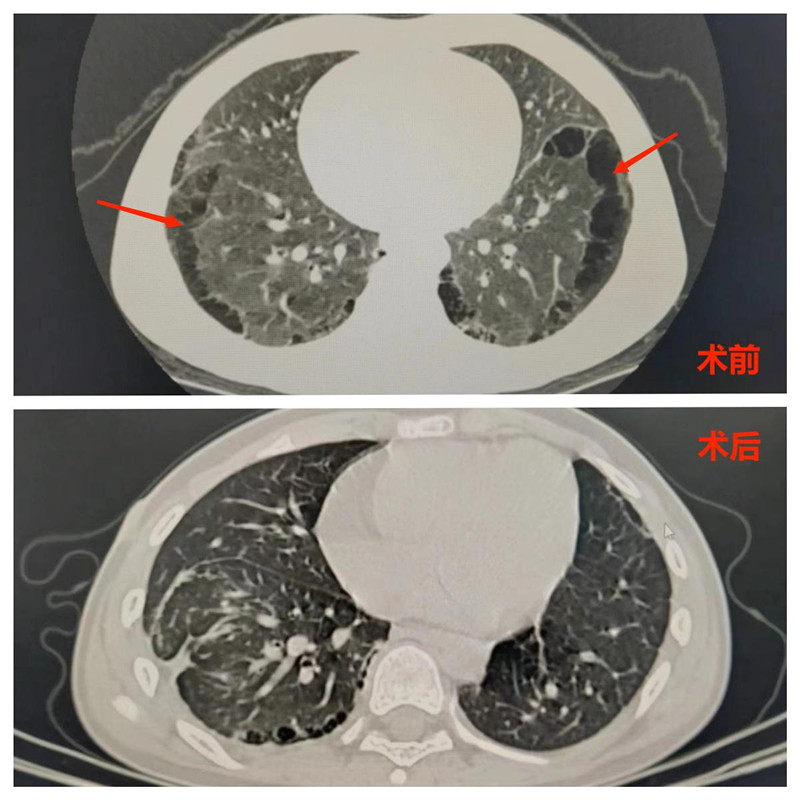

术前术后对比图。

杭杭家住湖北通城,从小体质差,三天两头生病。这次妈妈发现,半年里杭杭反复发烧、肺部感染,在小诊室打针吃药只是好了一阵。详细检查发现杭杭双肺5片肺叶布满了大小不一的囊性腺瘤。

据朱天琦介绍,肺囊性腺瘤畸形是一类气道、肺实质发育异常的先天性良性疾病,在CT上表现出来就像大小不一的囊性水泡。发病率约万分之四至万分之五,刚出生时,幼儿大多不会有任何不适,但随着年龄的增长,可能会发生反复的肺部感染,甚至成年后还有癌变的可能。大多数儿童肺囊腺瘤是单一存在的,但像杭杭这样,双肺表面到处都是大大小小的水泡,穿插在正常肺组织之间,非常罕见。

2023年3月和7月,同济医院小儿外科医生团队通过雾化吸入吲哚菁绿分两次为杭杭实施了胸腔镜下左、右侧肺叶先天性囊性病灶切除手术。两次手术都非常成功,术后杭杭也恢复得很好。